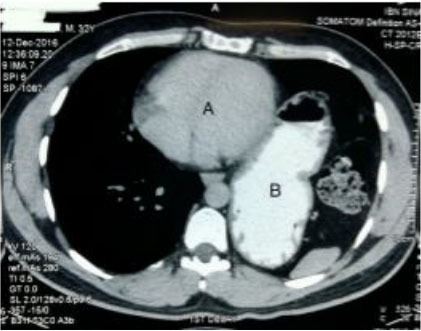

For further evaluation, contrast-enhanced computed tomography (CT) scan and an upper GI series were performed which demonstrated that almost the entire stomach occupied the left side of the mediastinal cavity above the left hemi-diaphragm (Figure 1 and Figure 2).

The stomach passed through a gap in the medial part of the left hemi-diaphragm. There was splitting of the muscle fibers of the left crus of the diaphragm near its insertion on the vertebra.

The gastroesophageal junction (GEJ) was in place but the gastro-duodenal junction was displaced supero-laterally on the left. Computed tomography films provided additional information suggestive of rotation of the stomach along its long axis, consistent with a partial gastric volvulus (Figure 1 and Figure 3). Chest X-ray (CXR) posteroanterior (P/A) view in erect posture revealed the position of the fundic gas shadow to be above the left hemi-diaphragm (Figure 4).

Figure 1: Contrast CT scan of abdomen, coronal section showing most of the stomach (A) above the left dome of the diaphragm (arrow).

Figure 3: CT scan of abdomen, transverse section, showing stomach (B) located in the chest cavity, adjacent to the heart (A).